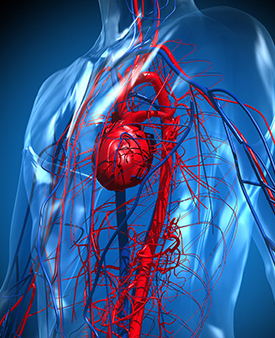

Deep vein thrombosis (DVT) and pulmonary embolism (PE) are known collectively as venous thromboembolism (VTE). Venous thromboembolic events are common and poten......

Increasing Circulation in the Lower Limb

The action of foot impulse technology (FIT) in reducing the risk of deep vein thrombosis (DVT) is well established. We hypothesized that intraoperative use of F......